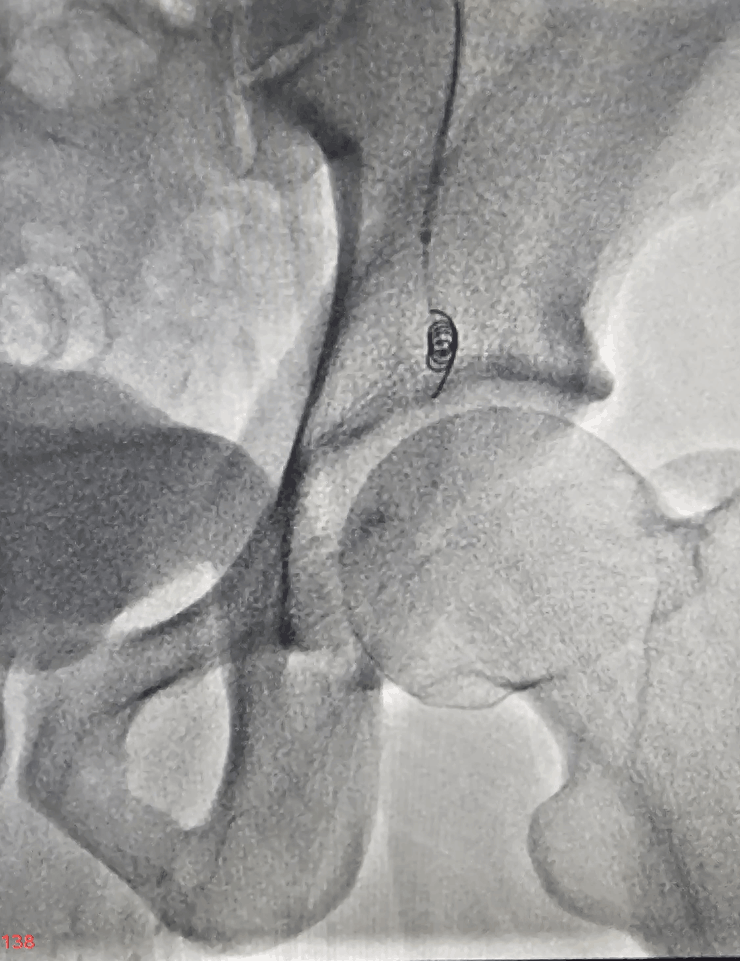

- Coil embolization and/or other embolic agents are used to block the refluxing veins.

- Completion check to ensure there is no further abnormal back‑flow to the scrotal veins.

Treating varicocele without surgery